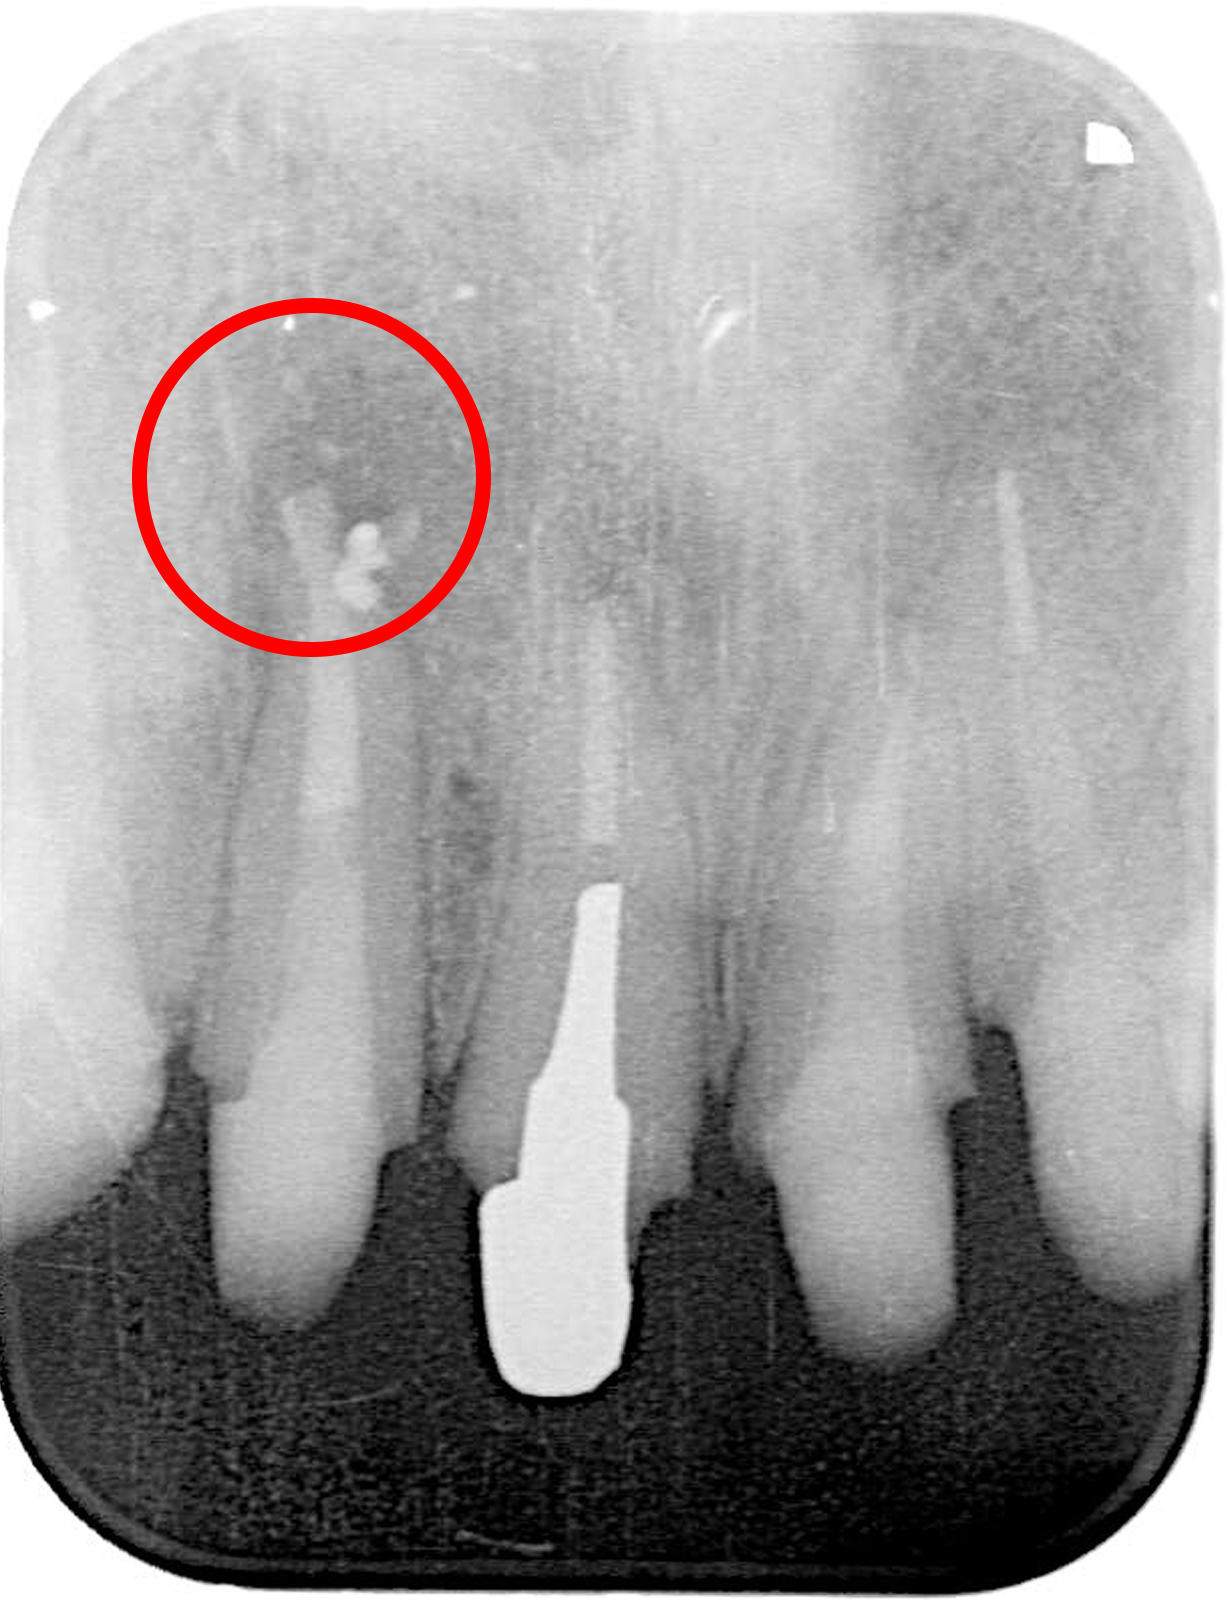

前医で根管治療を行った際、ファイルが破折して歯の中に残ってしまった症例。

超音波で振動を与えて破折ファイルを浮かせることで、安全に除去できる。